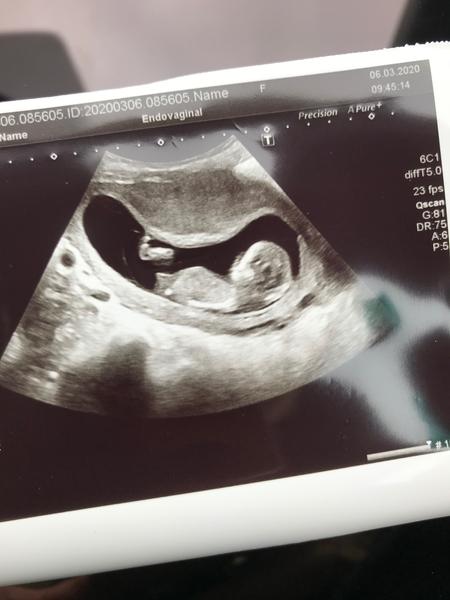

Holky vidíte něco tady ? je to ta menší fotka vlevo nahoře z Prenatalu ze 13.týdnu - z te celkove neni videt nic 🙂 nechali jsme si napsat do obálky od dr. Vlašína . V pondělí jdeme na druhý screening , necháme znova napsat pro jistotu a po něm už asi otevřeme (přítel to chce vědět 🙂 . Počítám od začátku tak nějak s klukem 🙂

@eiram7 holcicka 😊